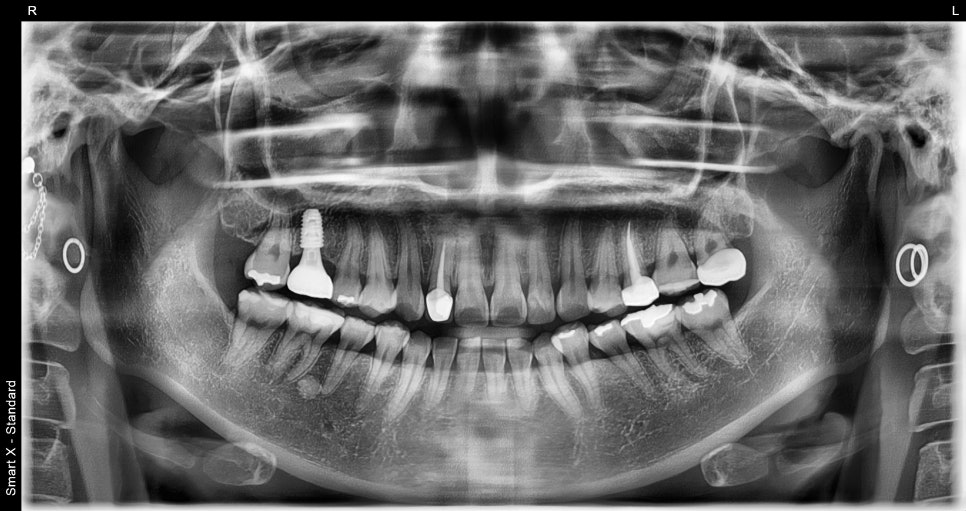

This patient was a 27-year-old woman who visited us because of aesthetic issues with an upper front tooth crown treated about 10 years ago.

A black line visible at the gums

A color difference from the surrounding teeth

An unnatural look in the front teeth

As time passes, upper front tooth crowns can look different from the original result as the gums recede or the internal structure changes. In such cases, rather than simple maintenance, it is necessary to improve them naturally through retreatment.